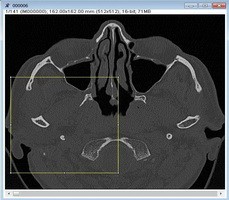

My Space 真實病人CT 成像模塊

操作者可以導(dǎo)入自己病人的CT 數(shù)據(jù),創(chuàng)建新的訓(xùn)練案例(可用于手術(shù)前預(yù)演)。幾分鐘之內(nèi),系統(tǒng)將提供一個可訓(xùn)練的骨模型。雖然危機組織無法在新的成像中自動標(biāo)注,而導(dǎo)航系統(tǒng)會同步在橫截面視圖中辨別方向,方便操作者學(xué)習(xí)及操作。